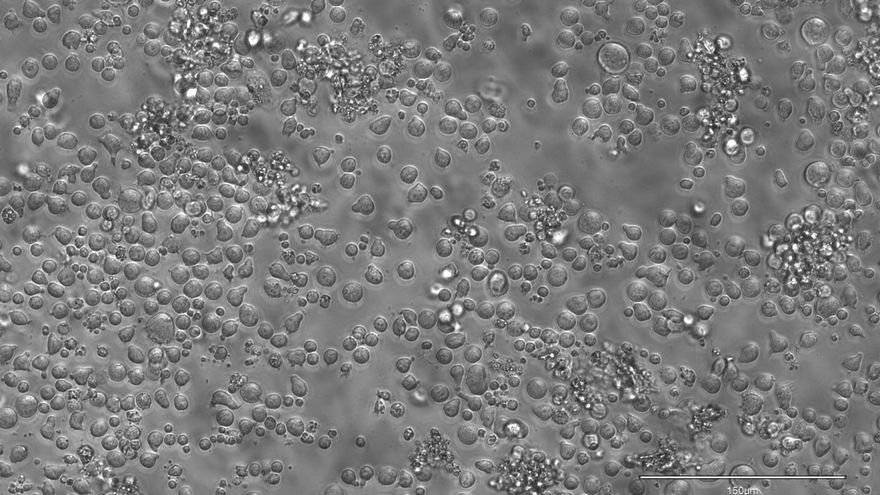

La técnica, llamada 'EPI-Clone', que lee estos códigos de barras en cada célula basándose en la plataforma Tapestri de Mission Bio para secuenciación de células individuales, permite reconstruir la historia de la producción sanguínea, identificando qué células madre contribuyen a la sangre (expandiéndose) y cuáles van abandonando la carrera (extinguiéndose) a lo largo del tiempo.

El estudio también descubrió que algunos clones grandes de células albergaban mutaciones relacionadas con la hematopoyesis clonal, un proceso en el que algunas células madre sanguíneas adquieren mutaciones que les permiten crecer y multiplicarse más rápido que otras.